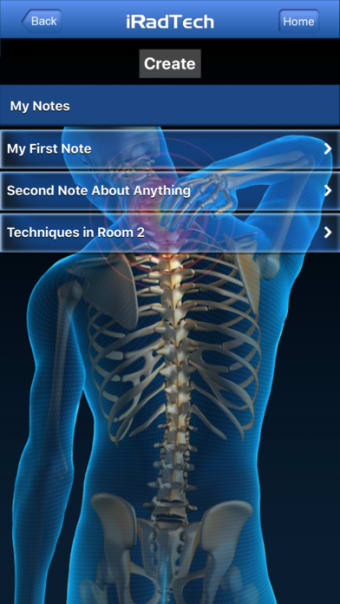

Un'applicazione versione completa per iPhone, di Ballinger e Bruckner LLP.

IRadTechè un programma completo per iPhone, che fa parte della categoria 'Medicina'.

IRadTech funziona su iOS 12.1.2 e versioni successive. La versione attuale dell'app è 4.0.1 e puoi eseguirla solo in inglese.